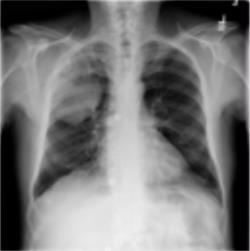

Thoracic disease detection from chest radiographs using deep learning methods has been an active area of research in the last decade. Most previous methods attempt to focus on the diseased organs of the image by identifying spatial regions responsible for significant contributions to the model's prediction. In contrast, expert radiologists first locate the prominent anatomical structures before determining if those regions are anomalous. Therefore, integrating anatomical knowledge within deep learning models could bring substantial improvement in automatic disease classification. This work proposes an anatomy-aware attention-based architecture named Anatomy X-Net, that prioritizes the spatial features guided by the pre-identified anatomy regions. We leverage a semi-supervised learning method using the JSRT dataset containing organ-level annotation to obtain the anatomical segmentation masks (for lungs and heart) for the NIH and CheXpert datasets. The proposed Anatomy X-Net uses the pre-trained DenseNet-121 as the backbone network with two corresponding structured modules, the Anatomy Aware Attention (AAA) and Probabilistic Weighted Average Pooling (PWAP), in a cohesive framework for anatomical attention learning. Our proposed method sets new state-of-the-art performance on the official NIH test set with an AUC score of 0.8439, proving the efficacy of utilizing the anatomy segmentation knowledge to improve the thoracic disease classification. Furthermore, the Anatomy X-Net yields an averaged AUC of 0.9020 on the Stanford CheXpert dataset, improving on existing methods that demonstrate the generalizability of the proposed framework.